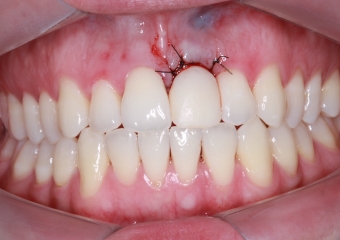

Foto Implante18-05-15